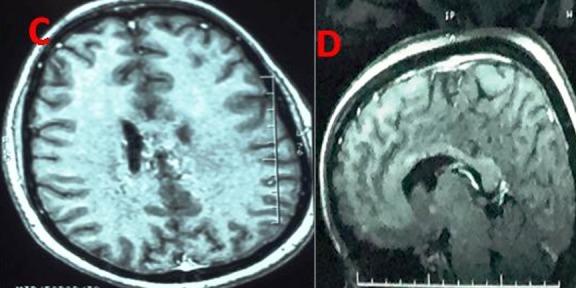

Tuberculosis is a major public health problem in developing countries. Cerebral tuberculomas is a tuberculous granulation tissue mass restrained and limited by immune defenses of the host. This study aims to describe the characteristics and the evolutionary profile of intracranial tuberculomas in Mauritania. Data of 34 patients with intracranial tuberculoma were collected retrospectively in several hospitals in the city of Nouakchott between January 2005 and June 2017. Evolutionary features of patients under treatment were analyzed. Our retrospective study involved 20 men and 14 women (sex ratio 1.4). The average age of our patients was 28.7 years. Twelve patients were less than or equal to 16 years. Symptomatology was dominated by increased intracranial pressure and seizures in 27 cases (79.41%) and 20 cases (58.82%) respectively. Intradermo tuberculin reaction was positive in 14 (41.17%) cases. Supratentorial lesion was found in 24 patients (70.58%). In all patients, therapeutic approach was based on multidrug chemotherapy for a period greater than or equal to 12 months. Surgical procedure was performed in 12 patients (35.29%). Outcome was favorable with complete healing without sequelae in 23 cases, reflecting a rate of 67.64%. Given the non-specific role of imaging exams in the diagnosis of intracranial tuberculoma and the lack of the stereotactic biopsy in our Country where the disease is endemic, we recommend to perform a two-month therapeutic test in patients with suspicious lesions.

结核病是发展中国家的一个主要公共卫生问题。脑结核瘤是一种受宿主免疫防御限制和局限的结核性肉芽组织肿块。本研究旨在描述毛里塔尼亚颅内结核瘤的特征和演变情况。2005年1月至2017年6月期间,在努瓦克肖特市的几家医院对34例颅内结核瘤患者的数据进行了回顾性收集。分析了接受治疗患者的演变特征。我们的回顾性研究纳入了20名男性和14名女性(性别比为1.4)。患者的平均年龄为28.7岁。12名患者年龄小于或等于16岁。症状以颅内压升高和癫痫发作为主,分别有27例(79.41%)和20例(58.82%)。结核菌素皮内反应阳性的有14例(41.17%)。幕上病变见于24例患者(70.58%)。所有患者的治疗方法均为多药化疗,疗程大于或等于12个月。12例患者(35.29%)接受了手术治疗。23例患者预后良好,完全愈合且无后遗症,愈合率为67.64%。鉴于影像学检查在颅内结核瘤诊断中的非特异性作用,以及在我们这个疾病流行的国家缺乏立体定向活检,我们建议对可疑病变患者进行为期两个月的治疗性试验。